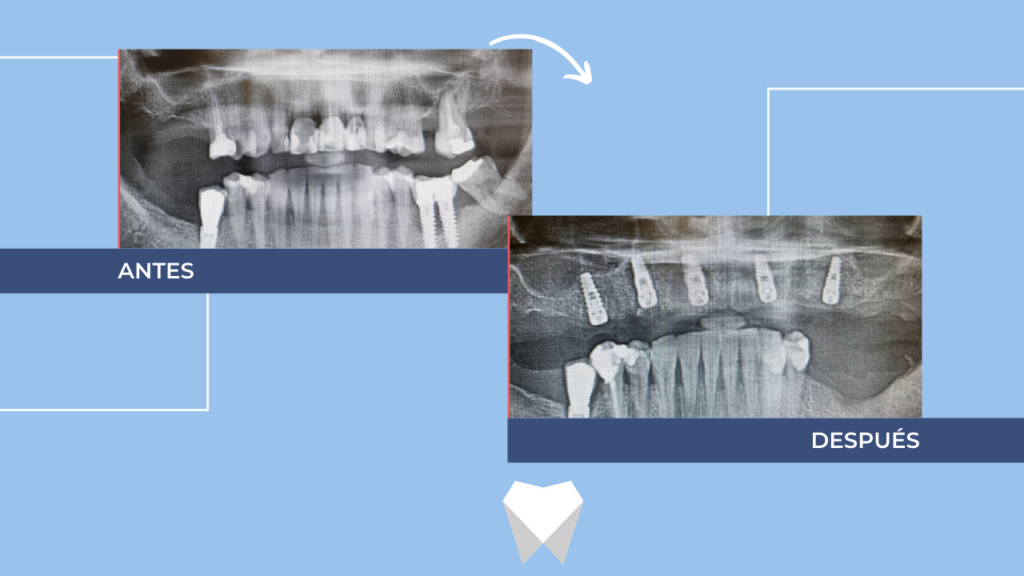

Hoy, te queremos enseñar uno de nuestros últimos casos, donde la colocación de implantes han sido la solución perfecta. El paciente tenía problemas de funcionalidad, ya que se le movían los dientes de la zona superior, y además no se sentía cómodo estéticamente con su aspecto. Tras valorar su caso de forma personalizada y realizar el diagnóstico, planificamos la extracción de las piezas superiores y la colocación de implantes para ese mismo día.

Mientras esperamos 4 meses a que termine el proceso de cicatrización para poder colocar la prótesis definitiva, se le ha puesto una dentadura completa provisional, para que pueda seguir disfrutando de su día a día.